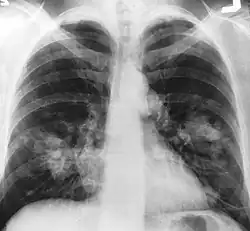

| An X-ray scan indicating abnormal masses in the lungs. | |